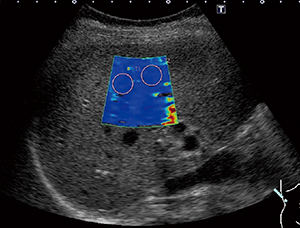

●Shear wave with Smart maps

プローブを静止した状態で,組織を圧迫することなく組織の硬さの絶対値を求めることができます。プローブからのPush Pulseによってせん断波を発生させ,その伝搬速度をカラーマッピング表示することにより,硬さの空間的分布を表示できます(図1)。これに加え,せん断波の到達時間を等高線表示する東芝独自の表示モードにより,せん断波の伝播状態を確認して検査結果の信頼性を判断することができます(図2)。

図1 カラーマッピング表示 |

図2 等高線表示 |

| (図1,2画像ご提供:兵庫医科大学・飯島尋子先生) | |